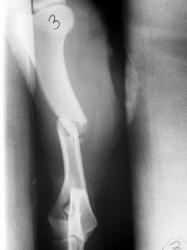

PRÁCTICAS CURSO DE FIJACIÓN EXTERNA PERFECCIONAMIENTO.

Húmero.